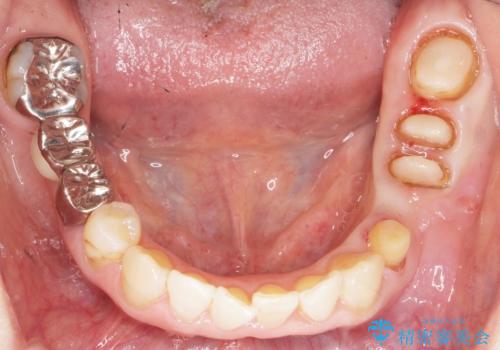

虫歯を丁寧に除去した後に歯根を分割し、骨を削合して健全歯質を露出させる骨外科手術を行いました。

手術後に根管治療を行い、歯肉と骨の治癒を十分に待った後ブリッジによる補綴治療を行いました。